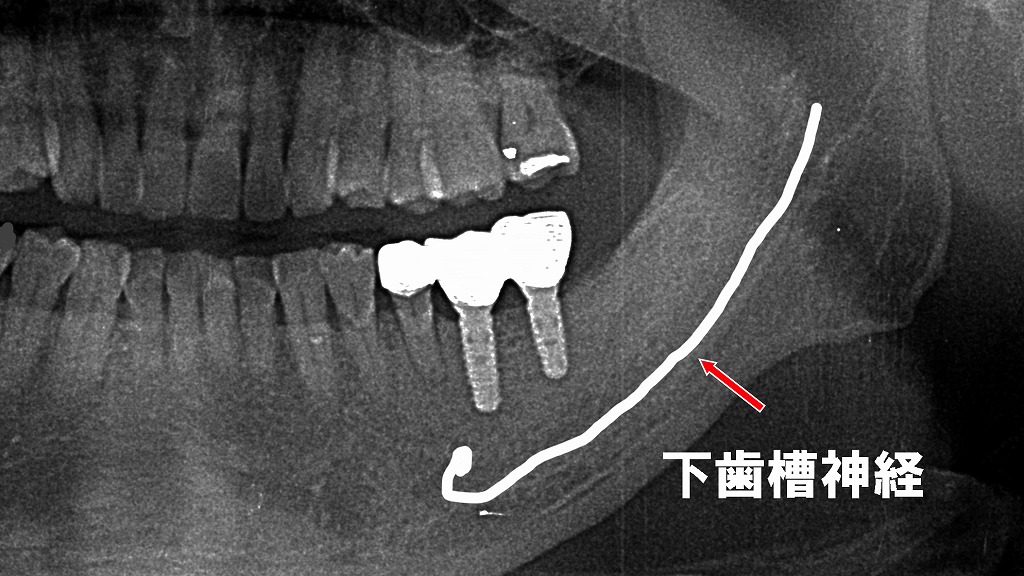

この画像は、左下6番・7番部にインプラント埋入後、オッセオインテグレーション(骨結合)を確認して上部構造を装着した段階で撮影されたパノラマレントゲンです。以下に詳しく解説します。

🦷 画像の概要

- 部位:左下6番・7番相当部

- 時期:インプラント埋入後の治癒期間(約3〜6か月)を経て、

オッセオインテグレーションが安定した状態で上部構造(クラウン)を装着したタイミングで撮影。

🔩 インプラントの状態

- 左下6番・7番部:

2本のインプラント体が明瞭に確認できます。

インプラント体は垂直的に安定しており、骨縁との境界に骨吸収はほとんど認められません。

オッセオインテグレーションが良好に得られていることを示しています。 - 上部構造:

ジルコニア製の連結冠が装着され、咬合関係も良好。

隣在歯との接触点・咬合面の高さも適正に設計されています。

⚡ 下歯槽神経との位置関係

- 画像上に示されている白線は下歯槽神経管の走行を示しています。

- インプラント体の先端と下歯槽神経管との距離が十分に確保されており、

神経損傷のリスクは極めて低い状態です。 - 安全域(一般的には2mm以上)が保たれており、術前のCTプランニング通りに埋入されています。

✅ 総合評価

- オッセオインテグレーションは良好。

- 骨吸収・感染所見なし。

- 下歯槽神経との距離も十分で、安全・安定したインプラント補綴が完成しています。

- 今後は定期的なメンテナンス(3〜6か月ごと)で骨吸収や清掃状態を確認していくことが望まれます。